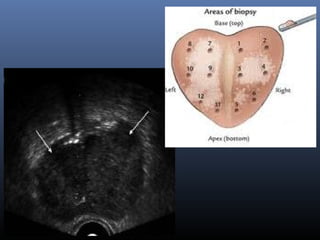

Görüntüleme Yöntemleri

1-Trans-rektal

Ultrasonografi

(TRUS):

 DRM bulgusu ve/veya

yüksek PSA seviyesi

(tanı ve biyopsi)

 TRUS ile, DRM’e göre

daha doğru bir yerel

evreleme